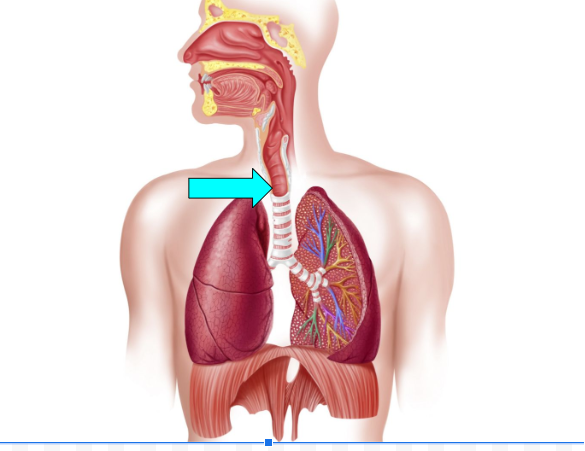

Trachea (pic)

Trachea

primary passageway for air to travel between lungs & the naval/oral cavity, mucus membrane traps dust particles & moistens/humidifies air